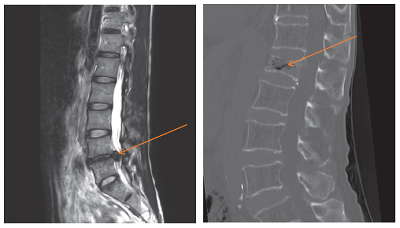

Figure 1 Slipped disc (Left); Figure 2 Spine fracture (Right)